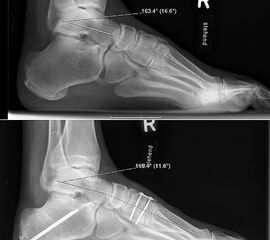

Lateralisierende Calcaneus-Osteotomie (Abb. 2 und 3, Video 2)

Die lateralisierende Calcaneus-Osteotomie ist ein Standard-Operationsschritt bei fast jeder Hohlfuβkorrektur. Der biomechanische Effekt der Osteotomie ist eine Verschiebung des Fersenkontaktpunktes und damit der beim Rückfuβ varus medialisierten Belastungsachse durch das OSG nach lateral. Diese statische Rückfuβ-Korrektur allein ist in der Lage, den bei Pes cavovarus anteromedial erhöhten OSG-Druck, der sehr wahrscheinlich zur korrespondierenden Arthrose führt, zu neutralisieren 7. Zuklappende Osteotomien mit Entnahme eines lateralen Knochenkeils haben sich dabei weniger effektiv gezeigt als solche mit Lateralisation des Tubers. Mit der Lateralisation des Achilles-Ansatzes verringert sich die Inversionskraft der Sehne zugunsten der schwachen Eversion, wodurch gleichzeitig die Prädisposition für Supinationstraumata reduziert wird. Neben der klassischen Dwyer-Osteotomie (Entnahme eines lateralen, vertikalen Keils 8 haben sich vor allem die technisch einfache Verschiebe-Osteotomien („sliding osteotomy“) und die Z-förmigen Osteotomien (Pisani 1993, Malerba 9) mit Entnahme eines lateralen Keils aus dem horizontalen Anteil der Osteotomie aber ohne Lateralisation des Tuberfragmentes, sowie die Korrektur nach Hintermann (Knupp 2008) mit zusätzlicher Lateralisation des Tuberfragmentes) durchgesetzt. Bei neutral aligniertem OSG ist keine supramalleoläre Tibia-Osteotomie zur Korrektur des Rückfuβ varus indiziert. Generell sollten Osteotomien gegenüber korrigierenden Arthrodesen der Vorzug gegeben werden. Die im Folgenden beschriebene Verschiebeosteotomie ist technisch einfach und hinsichtlich OSG-Druckneutralisation ebenso effektiv wie die Z-Osteotomien 7.

• Umfahren des Calcaneus mit Hohmann Hebeln und Markieren der Osteotomie mit 2 1.6 Kirschnerdrähten; Kontrolle der korrekten Osteotomie-Ebene im BV, diese sollten, da in der Regel keine Verkürzung oder Verlängerung des Rückfuβes gewünscht ist, in der axialen Projektion genau rechtwinklig zur Achse des Calcaneus verlaufen; seitlich beginnt die Osteotomie proximal etwa 2 cm anterior des Achilles-Ansatzes und läuft etwas schräg nach distal-anterior.

• Kontrolle der korrekten Schraubenlage im BV (Abb. 3).